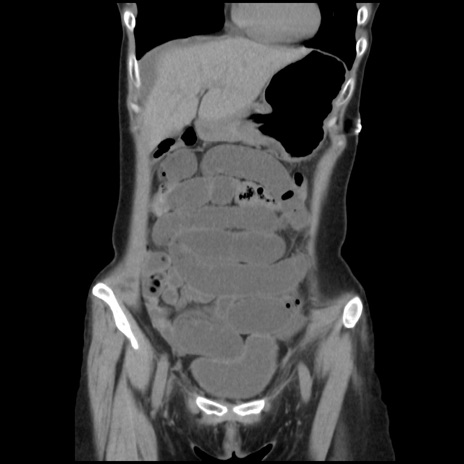

矢状断像

【症例】40歳代 女性

【主訴】上腹部痛、嘔気・嘔吐

【現病歴】約9時間前頃から急に上腹部痛、嘔気、嘔吐が出現。改善しないため救急要請。

【既往歴】子宮頚癌(広汎子宮全摘術、放射線療法)、腸閉塞

【身体所見】腹部:平坦、軟、腸雑音亢進、上腹部を中心に腹部全体に圧痛あり。

【データ】WBC 8400、CRP 0.03